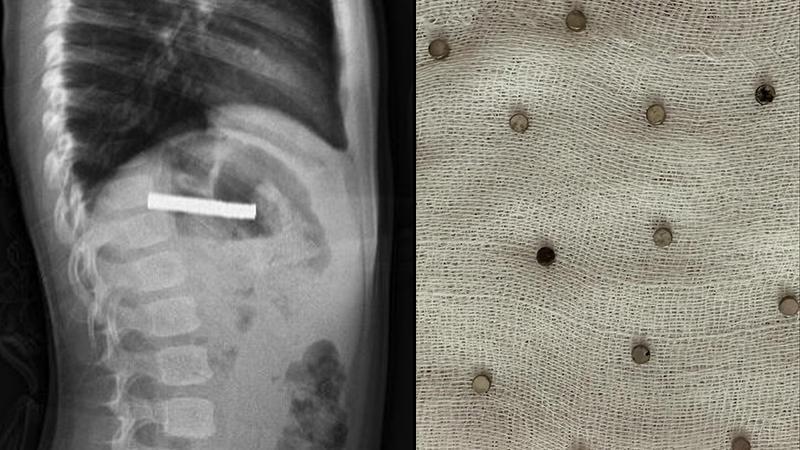

3 yaşındaki çocuğun yuttuğu 19 mıknatıs endoskopiyle çıkarıldı

Fırat Üniversitesi Tıp Fakültesi Çocuk Gastroenteroloji, Hepatoloji ve Beslenme Bilim Dalı Başkanı Prof. Dr. Yaşar Doğan ve ekibi tarafından gerçekleştirilen operasyonla, çocuğun yemek borusuna yapışan 19 mıknatıs endoskopik yöntemle çıkarıldı.

Mıknatısların, mide girişinde ve yemek borusunda zedelenmelere yol açtığı belirtildi. Çocuk tedavisinin ardından taburcu edildi.